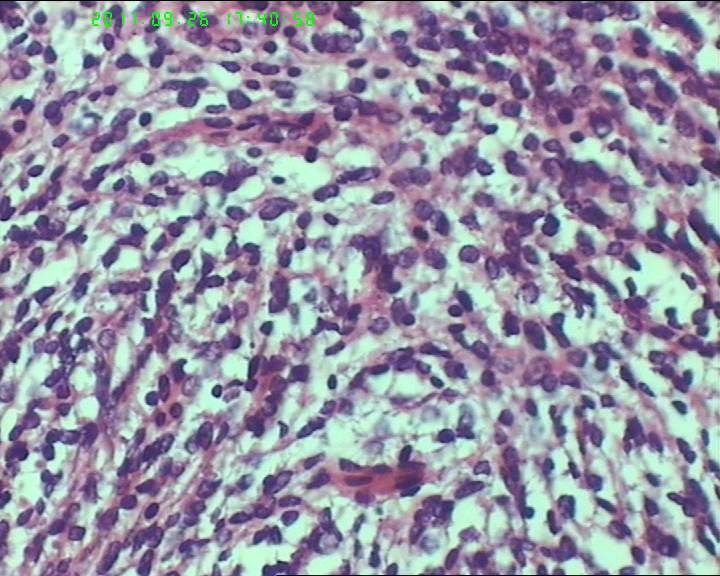

灰白不整形肿物一个,大小18*15*9cm,表面结节状,包膜完整,切面灰白,中央可见坏死区,质软,范围5*4cm。其余切面多彩 部分半透明状 质中。

鉴别诊断排排队:1、GIST,2、MPNST,3、去分化脂肪肉瘤,4、恶性间皮瘤,5、恶性SFT,6、平肉

主要考虑前二者。CD34,CD117,S-100,BCL-2,SMA, D2-40,CR, VIM. 结果如何?请楼主揭谜底吧。